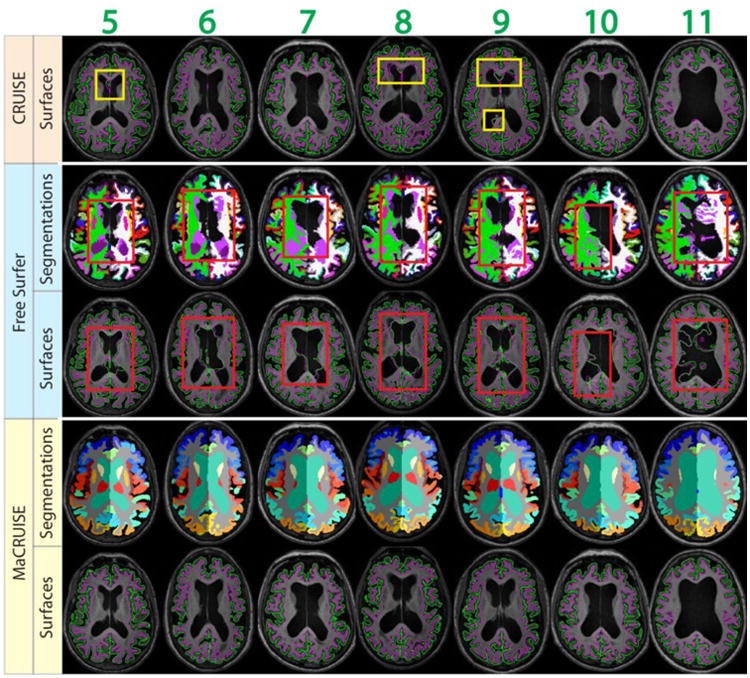

Mean ASD between MaCRUISE and the benchmark algorithms are generally around or smaller than 0.5 mm (Figure 10a). However, there are four images (marked using red numbers 1 through 4) that are located outside of a margin of 2.5 standard deviations. These large surface distances indicate that at least one of the methods failed with these images. For the ventricle volumes, a strong linear correlation was found except in seven outlier volumes (marked using green numbers 4 through 11) (Figure 10b). Thus, a total of 11 failed volumes were automatically detected. The segmentations and surfaces of the failures for these subjects are shown in Figure 11 (red outliers) and Figure 12 (green outliers). The global failures (in the red rectangles) occur in all 11 volumes for FreeSurfer and in two volumes for CRUISE. In contrast, we do not find any global failures from MaCRUISE. Therefore, none of the 11 failures are attributable to MaCRUISE. To complete the analysis, we visually inspected the surfaces and segmentations for the remaining 189 volumes and did not find any global failures for either MaCRUISE or the benchmark algorithms.

Fig. 11.

The four outliers from surface distance analysis are shown. Both whole brain segmentations and cortical surfaces on axial slices are provided. The areas in red rectangles show the global failures in FreeSurfer whereas MaCRUISE did not exhibit any such failures.

Fig. 12.

The seven outliers from inconsistent lateral ventricle size are shown. Both whole brain segmentations and cortical surfaces on axial slices are provided. The areas in red rectangles show the global failures while the areas in yellow rectangles show the local inaccurate surfaces. MaCRUISE did not exhibit such failures in any images.